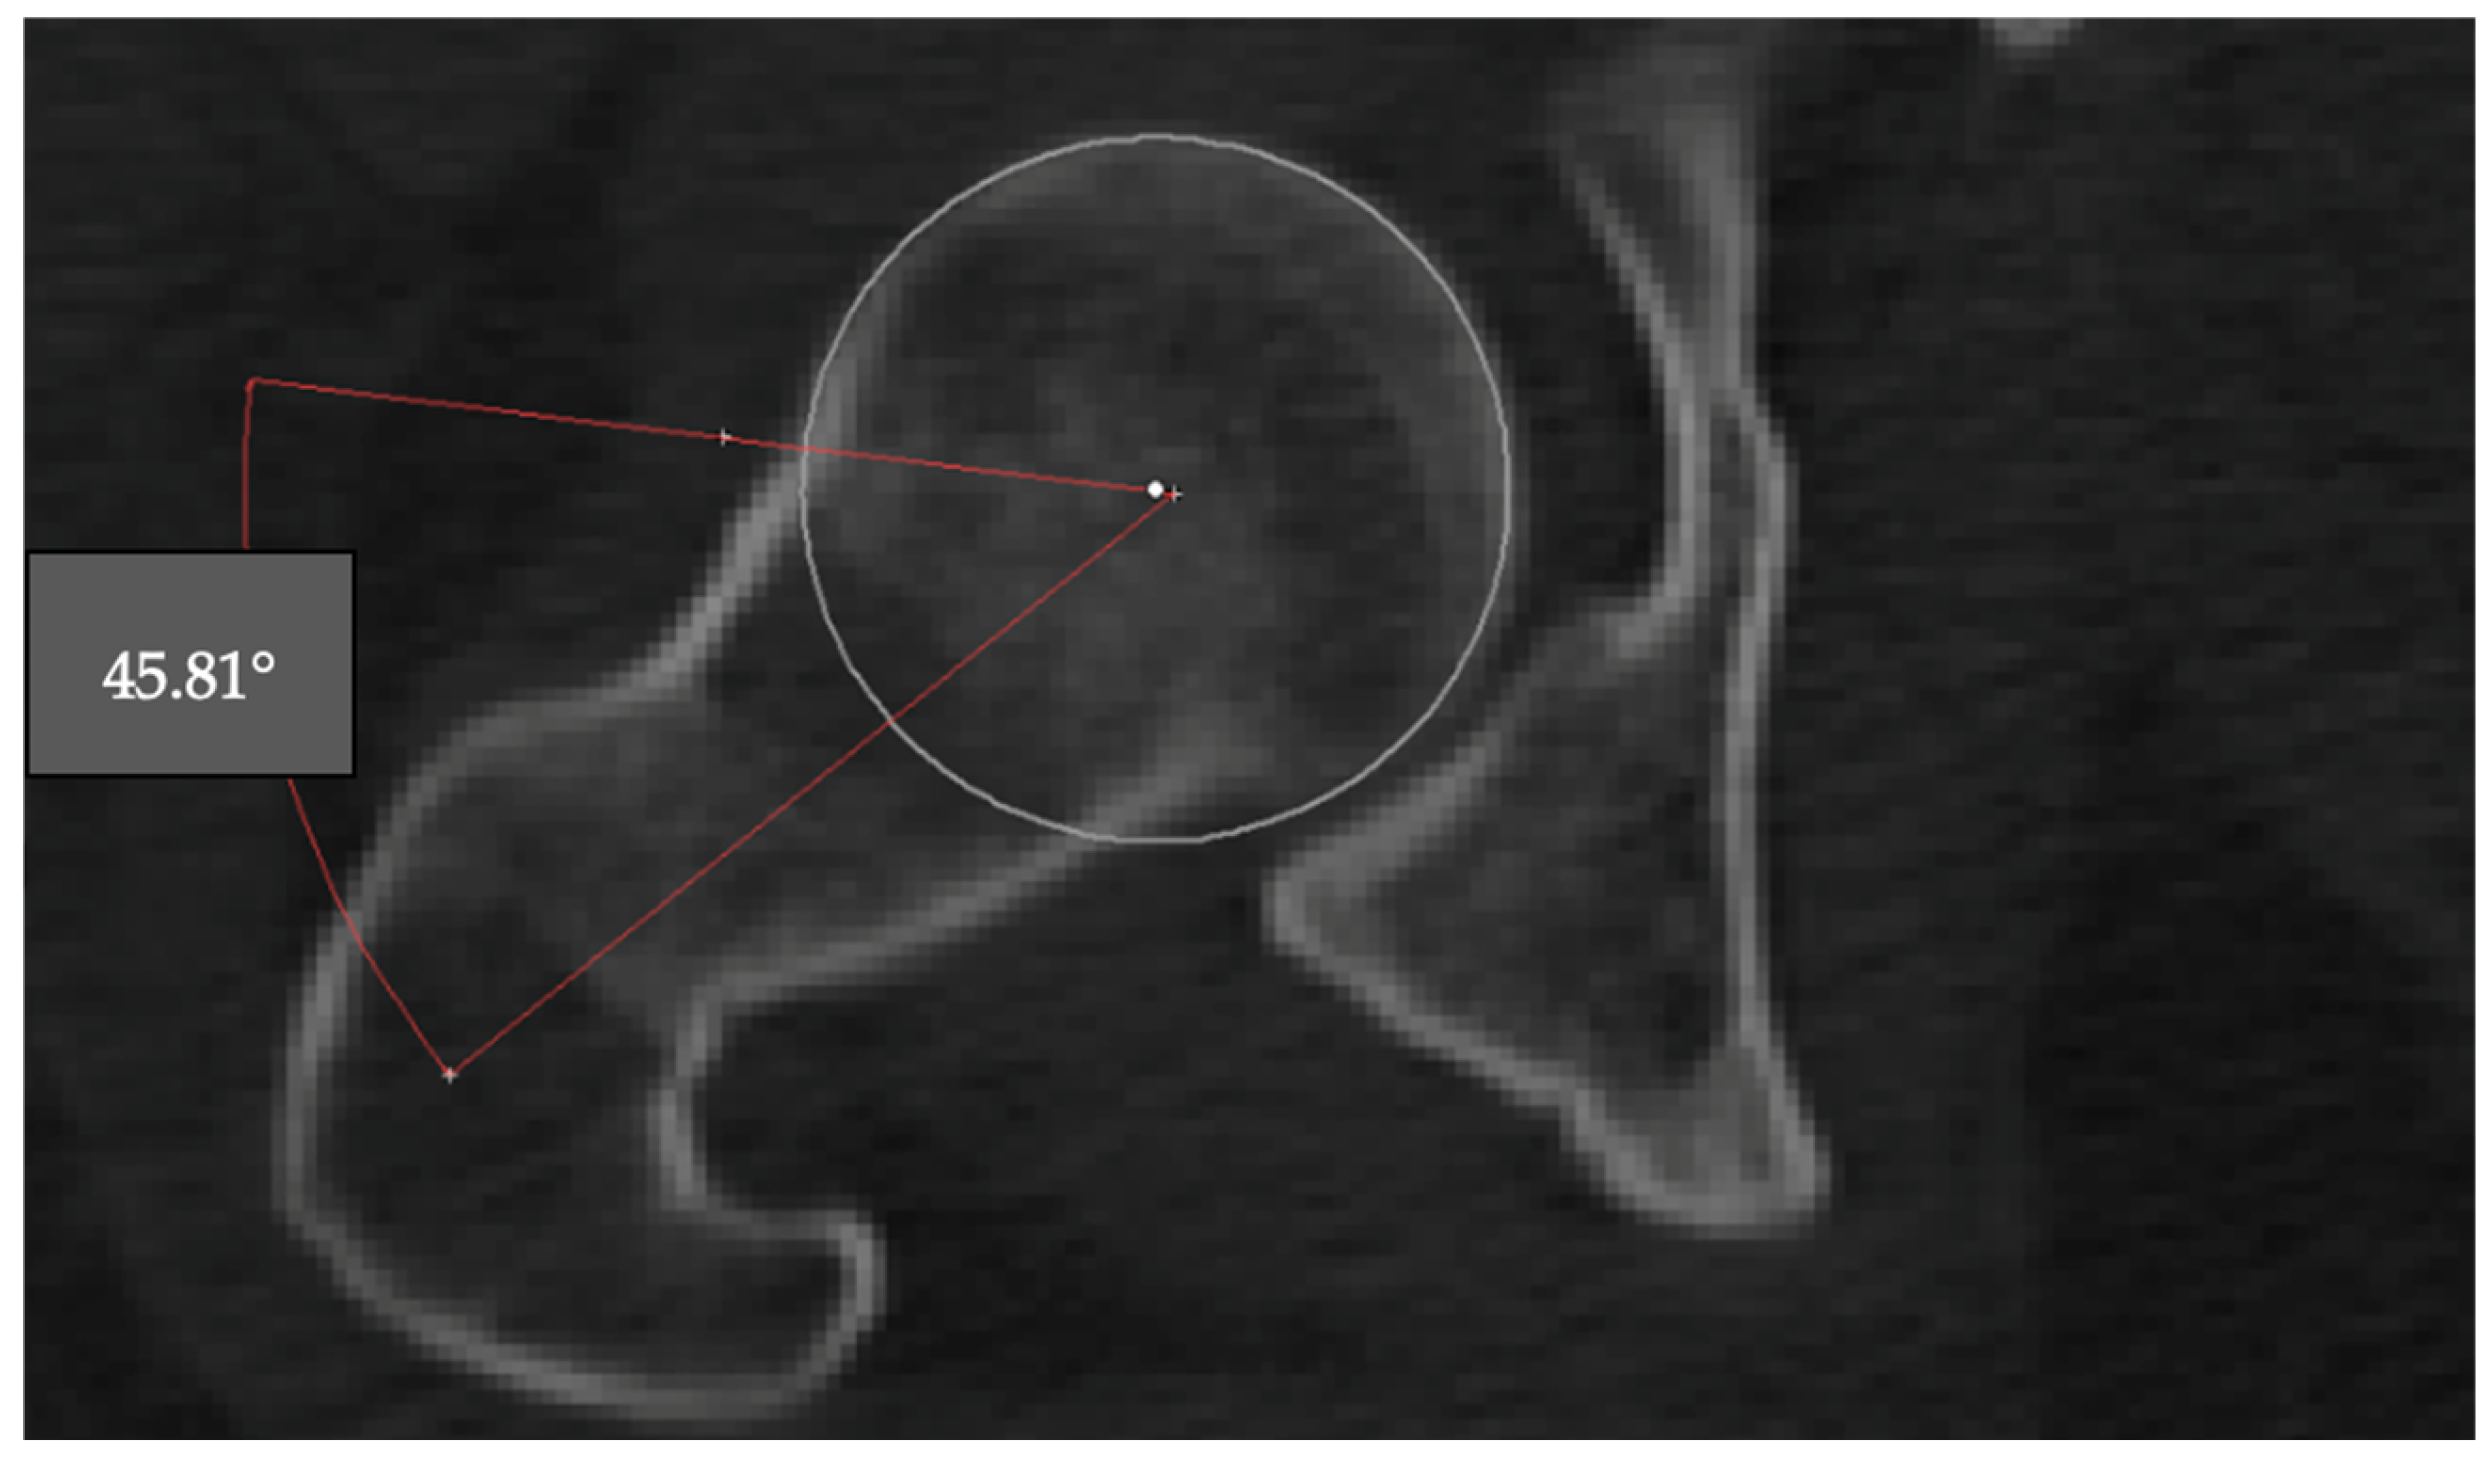

2.1.2. Alpha Angle

The alpha angle is used to assess the sphericity of the femoral head and detect cam-type deformities. The angle was measured on the axial CT slice where the femoral head appeared largest. A best-fit circle was drawn around the subchondral bone of the femoral head, and two lines were drawn: one from the center of the femoral head through the neck axis, and another from the center to the point where the femoral head extended beyond the circular contour. The angle between these two lines was recorded as the alpha angle (Figure 2).

Figure 2. Measurement of the alpha angle on an axial CT slice. The angle is formed between the femoral neck axis and a line drawn from the femoral head center to the point where the head contour deviates from the best-fit circle (45.81°).